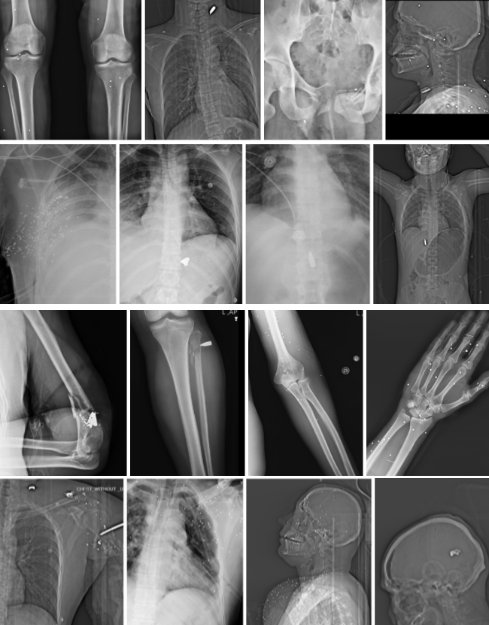

در این گزارش، فکتنامه و گاردین ۷۸ تصویر پزشکی را که از یک بیمارستان در یکی از شهرهای بزرگ ایران به طور مستقل تایید و بررسی کردهاند. تصاویر، مربوط به ۶۴ فرد آسیبدیده است. این تصاویر شامل ۲۹ عکس از نوع X-Ray و ۴۷ مورد تصویر CT و دو مورد CTA (مربوط به یک مجروح) است که همراه با اطلاعاتی مثل زمان دقیق تصویربرداری، ناحیه یا نواحی تحت بررسی، نام، جنسیت و در برخی موارد وضعیت سنی بیمار در اختیار فکتنامه قرار گرفته است. این تصاویر همچنین حاوی دادههایی درباره مراکز درمانی و مشخصات بیماران بودهاند که بهصورت کامل نزد تیم تحقیق محفوظ ماندهاند.

راستیآزمایی اولیه تصاویر، بدون افشای هویت منابع انجام شده است. علاوه بر اطمینان پیدا کردن از منابع، وجود جزئیات فنی مانند نام بیمار، تاریخ و ساعت دقیق تصویربرداری، نام مرکز تصویربرداری و هماهنگی این دادهها با محتوای بصری تصاویر، از جمله نشانههای اصالت این اسناد بوده است. در تصاویر دریافتی، نشانهای از دستکاری دیجیتال، کپیکاری، ناسازگاری آناتومیک، کنتراست غیرطبیعی، بریدگیهای مشکوک یا تکرار الگوهای مصنوعی پیدا نشد و مجموعهای از شاخصها، حاکی از واقعیبودن تصاویر و تهیه آنها در مراکز درمانی است. تصاویر، در اختیار تعدادی از پزشکان متخصص اورژانس و همچنین کارشناس گلولهشناسی قرار دادهشد. الگوی تغییر شکل پرتابه و محل ورود و جایگیری آن، تایید میکند که این تصاویر به بدنهای واقعی آسیبدیده بر اثر شلیک گلوله یا ساچمه تعلق دارند.

چهار الگوی تیپیک در تصاویر پزشکی: ساچمههای شاتگان در سر و اندام، آسیب پرانرژی در لگن، و گلوله در گردن با جابجایی نای و خطر آسیب عروق بزرگ.

تصاویر رادیولوژی نشان میدهد که در این مجموعه، دو الگوی غالب شلیک قابل تفکیک است: آسیبهای ناشی از ساچمههای شاتگان و آسیبهای ناشی از گلولههای پرسرعت کالیبر ۷٫۶۲. تشخیص این موارد بر اساس اندازه، شکل، تعداد، نحوه پراکندگی، تغییر شکل فلزی و مسیر احتمالی حرکت پرتابه در بدن، از تصاویر واضح است.

در موارد مربوط به ساچمههای شاتگان، تصاویر معمولا چندین جسم فلزی کوچک با چگالی بالا را نشان میدهند که به صورت پراکنده یا خوشهای در بافت نرم، اطراف مفاصل یا در ناحیه صورت و سر قرار گرفتهاند. در برخی تصاویر، الگوی پراکندگی ساچمهها با یک «مخروط پراکندگی» سازگار است که میتواند با فاصله متوسط یا نزدیک شلیک همخوانی داشته باشد. در تصاویر این مجموعه، دامنهای از الگوهای پراکندگی دیده میشود؛ از خوشههای فشرده که با فاصلههای کوتاه سازگارند، تا پراکندگیهای وسیعتر که میتواند نشاندهنده فاصلههای متوسط یا بیشتر باشد. در برخی موارد، تمرکز ساچمهها بر یک ناحیه حیاتی خاص، مانند سر یا صورت دیده میشود. چنین تراکمی معمولا با انتقال انرژی بالا به بدن همراه است و میتواند منجر به خردشدگی استخوان، پارگی گسترده بافت نرم و در مواردی آسیبهای تهدیدکننده حیات شود. شدت این الگوها، بهویژه در نواحی سر، گردن و قفسه سینه، نشاندهنده اعمال نیروی قابل توجه است؛ هرچند شدت آسیب همواره تابع ترکیبی از فاصله، نوع مهمات، زاویه برخورد و وضعیت بدن فرد بوده است.

A) شلیک ساچمهای (Birdshot)؛ ۴۵ مورد

بیشترین سهم موارد، به مهمات ساچمهای شاتگان، بهویژه بردشات گیج ۱۲، تعلق دارد که در ۴۵ مورد شناسایی شده است. این موارد در تصاویر X-ray و CT عمدتا با حضور چندین جسم فلزی کوچک و پرچگال، با اندازه و شکل نسبتا یکنواخت، در یک یا چند ناحیه بدن مشخص میشوند.

در توصیفهای پزشکان، الگوی تکرارشونده شامل پراکندگی متعدد ساچمه در سر و صورت، اطراف اوربیت، گردن و اندامهاست. موارد متعددی از آسیب چشمی با خطر نابینایی دائمی ذکر شده و در برخی پروندهها، ساچمهها در سینوسها، قاعده جمجمه یا مجاورت ستون فقرات گردنی مشاهده شدهاند. در چند مورد، علاوه بر آسیب نرمبافتی گسترده، احتمال درگیری عروق بزرگ یا خطر خونریزی شدید مطرح شده است. در آسیبهای سر و گردن، برخی ارزیابیها بهصراحت به ریسک بالای مرگ یا پیامدهای عصبی پایدار اشاره کردهاند؛ بهویژه زمانی که تراکم ساچمهها در یک ناحیه محدود و حیاتی بالا بوده است.